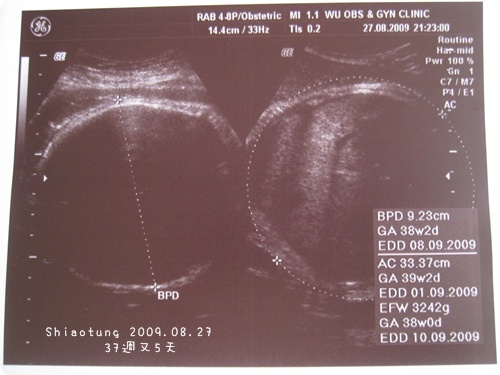

胎兒體重:約32xxg

醫生說目前大概有3200g,

08.27-37w+5...已經聽說要來到32xxg→3242g左右